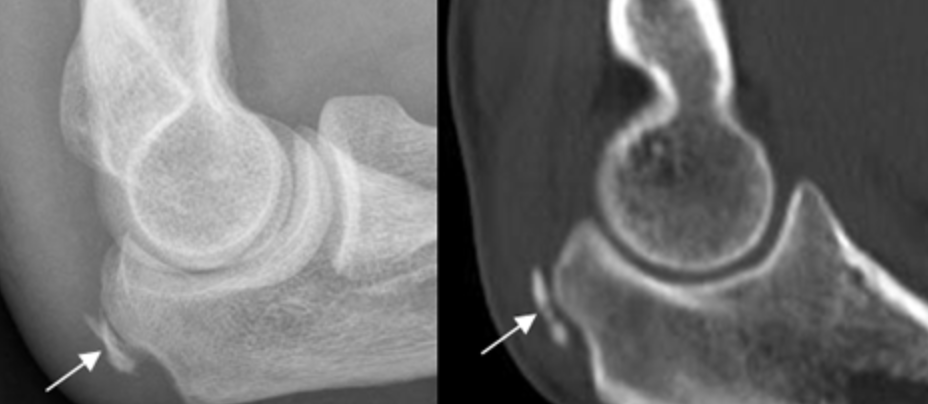

Fractura multifragmentada de cúpula radial: En estas radiografías se puede observar como luce una fractura aislada de la cabeza de radio. Según el trazo o su clasificación se indicará tratamiento desde portar un cabestrillo, síntesis o cirugía para restaurar su forma y dar estabilidad e incluso una sustitución de la cúpula radial.

Fractura de cúpula radial: Fractura desplazada, visión lateral.